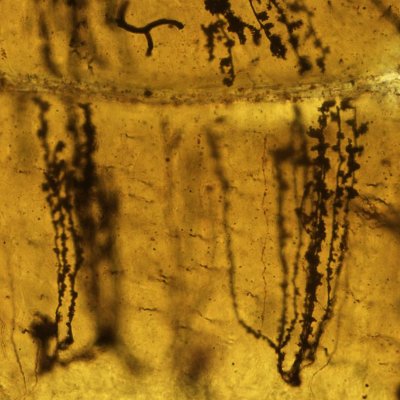

Cerebelo